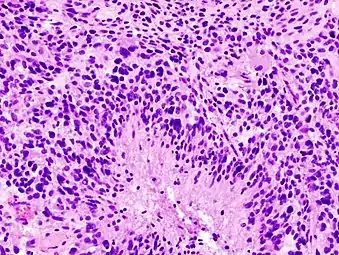

Brain tumor classification has been traditionally based on histopathology at macroscopic level, measured in hematoxylin-eosin sections. The World Health Organization published the first standard classification in 1979[33] and has been doing so since. The 2007 WHO Classification of Tumors of the Central Nervous System[34] was the last classification mainly based on microscopy features. The new 2016 WHO Classification of Tumors of the Central Nervous System[35] was a paradigm shift: some of the tumors were defined also by their genetic composition as well as their cell morphology.

When viewed with MRI, glioblastomas often appear as ring-enhancing lesions. The appearance is not specific, however, as other lesions such as abscess, metastasis, tumefactive multiple sclerosis, and other entities may have a similar appearance.[58] Definitive diagnosis of a suspected GBM on CT or MRI requires a stereotactic biopsy or a craniotomy with tumor resection and pathologic confirmation. Because the tumor grade is based upon the most malignant portion of the tumor, biopsy or subtotal tumor resection can result in undergrading of the lesion. Imaging of tumor blood flow using perfusion MRI and measuring tumor metabolite concentration with MR spectroscopy may add diagnostic value to standard MRI in select cases by showing increased relative cerebral blood volume and increased choline peak, respectively, but pathology remains the gold standard for diagnosis and molecular characterization.

Distinguishing glioblastoma from high-grade astrocytoma is important. These tumors occur spontaneously (de novo) and have not progressed from a lower-grade glioma, as in high-grade astrocytomas[6] Glioblastomas have a worse prognosis and different tumor biology, and may have a different response to therapy, which makes this a critical evaluation to determine patient prognosis and therapy.[45][59] Astrocytomas carry a mutation in IDH1 or IDH2, whereas this mutation is not present in glioblastoma. Thus, IDH1 and IDH2 mutations are a useful tool to distinguish glioblastomas from astrocytomas, since histopathologically they are similar and the distinction without molecular biomarkers is unreliable.[46] IDH-wildtype glioblastomas usually have lower OLIG2 expression compared with IDH-mutant lower grade astrocytomas.[60]